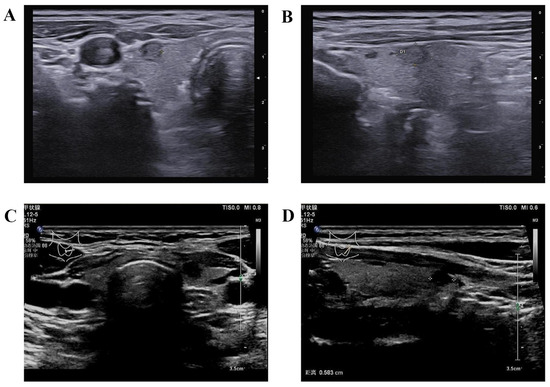

- Hong, Y.R.; Yan, C.X.; Mo, G.Q.; Luo, Z.Y.; Zhang, Y.; Wang, Y.; Huang, P.T. Conventional US, elastography, and contrast enhanced US features of papillary thyroid microcarcinoma predict central compartment lymph node metastases. Sci. Rep. 2015, 5, 7748. [Google Scholar] [CrossRef] [PubMed]

- Tao, L.; Zhou, W.; Zhan, W.; Li, W.; Wang, Y.; Fan, J. Preoperative Prediction of Cervical Lymph Node Metastasis in Papillary Thyroid Carcinoma via Conventional and Contrast-Enhanced Ultrasound. J. Ultrasound Med. Off. J. Am. Inst. Ultrasound Med. 2020, 39, 2071–2080. [Google Scholar] [CrossRef] [PubMed]

- Wang, Y.; Nie, F.; Wang, G.; Liu, T.; Dong, T.; Sun, Y. Value of Combining Clinical Factors, Conventional Ultrasound, and Contrast-Enhanced Ultrasound Features in Preoperative Prediction of Central Lymph Node Metastases of Different Sized Papillary Thyroid Carcinomas. Cancer Manag. Res. 2021, 13, 3403–3415. [Google Scholar] [CrossRef]